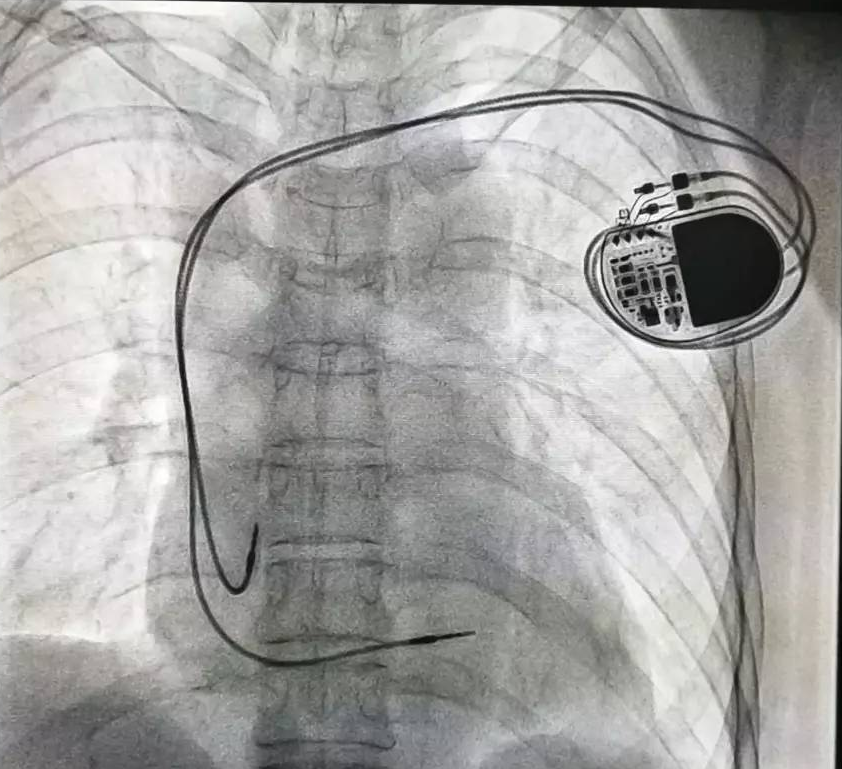

全球唯一!無(wú)線(xiàn)雙腔起搏器首次植入

來(lái)源:器械之家,未經(jīng)授權(quán)不得以任何形式轉(zhuǎn)載,且24小時(shí)后方可轉(zhuǎn)載。2022年2月7日雅培宣布,其在研型Aveir?雙腔無(wú)引線(xiàn)起搏器完成了全球首例患者植入,這也是全世界第一個(gè)雙腔無(wú)線(xiàn)起搏器。Aveir?DR雙腔起搏器提供右心房和心臟右心室的同步、逐次跳起搏,近80%接受起搏器治療的患者需要雙腔選擇,A